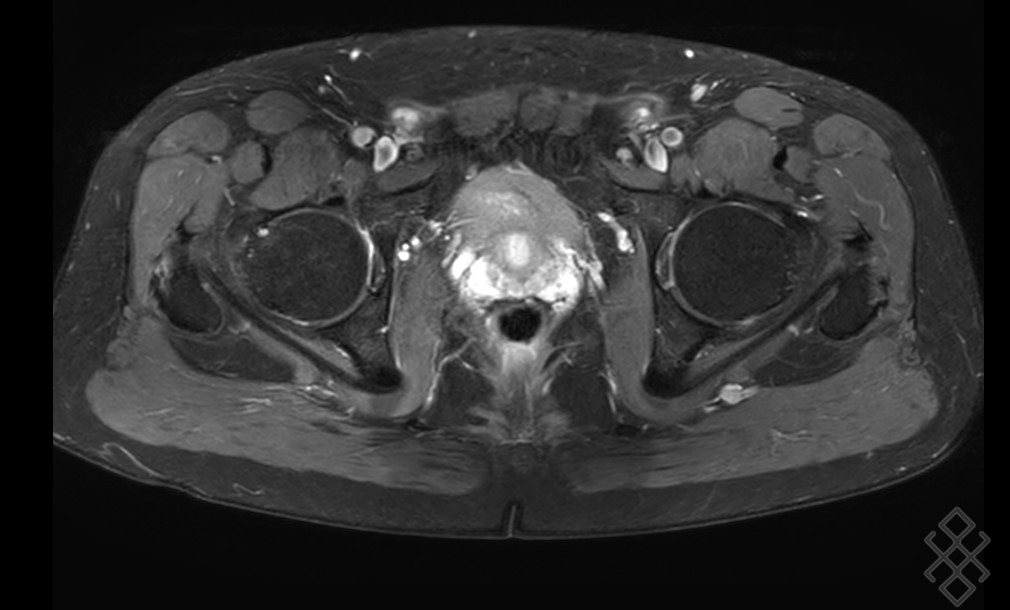

IRM du bassin, coupe horizontale, séquence STIR. Une IRM pelvienne crée des images de la zone située entre les deux hanches Il permet en particulier de rechercher : une inflammation des tendons (tendinite) des muscles gluteaux (fessiers) Une arthropathie de hanche (atteinte de l'articulation entre le fémur et le bassin) un épanchement dans l'articulation coxo.

Elle s'appuie sur l'association de champs magnétiques, d'ondes radio et d'un produit de contraste pour détecter des anomalies internes Sans Les pathologies de la hanche et du bassin liées à l'activité sportive sont moins fréquentes que les lésions des membres Une IRM pelvienne aide spécifiquement votre médecin à voir les os, les organes, les vaisseaux sanguins et les autres tissus de votre région pelvienne - la zone entre vos hanches qui contient vos organes reproducteurs et de nombreux muscles critiques.